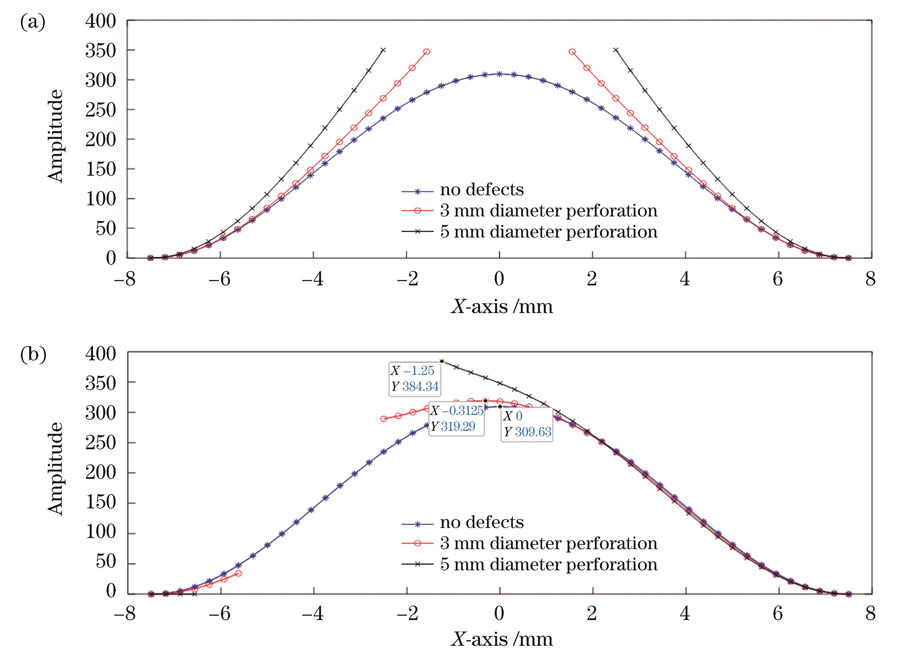

图 4. y=0处的振幅分布截面图。(a)中心穿孔薄膜;(b)偏心穿孔薄膜

Fig. 4. Section of amplitude at y=0. (a) Central perforated film; (b) eccentric perforated film

First, the theoretical analysis proves that using the spatial carrier phase extraction method to detect the amplitude distribution in eardrum samples in the vibration mode is reasonable. In the finite element simulation and experimental analysis, the vibration modes of the artificial eardrums with defects were analyzed, and the results showed that different defects affect the amplitude distribution in the first-order vibration mode for the eardrums differently. For the perforated eardrum samples, the amplitude distribution was analyzed by varying the size and location of the perforation. The results show that the amplitude near the perforation increases significantly with the increase in perforation size (Figs. 3 and 4), and an increase in the number of fringes is observed in the experimental results (Fig. 11). By changing the location of the perforation, the maximum amplitude shifts off-center with the perforation, and the larger the perforation, the more evident the deviation. The amplitude distribution for the scratched eardrum samples was analyzed by varying the size and location of the scratch. The results show that at the same location, the larger the scratch length, the larger the surface amplitude of the film (Fig. 5), and the amplitude changes more significantly near the scratch location (Fig. 6). The experimental results show an increase in the number of fringes, and the shape of the fringe near the central scratch is flat (Fig. 12). When the scratch is off-center, the effect on the amplitude near the scratch is significantly greater than that at the center. The amplitude distribution for the calcified eardrum samples was analyzed by varying the thickness of the calcified layer (Fig. 7). The amplitude of the film decreases with an increase in the thickness of the calcified layer but is more evident at the location of the calcified layer (Figs. 8 and 13).